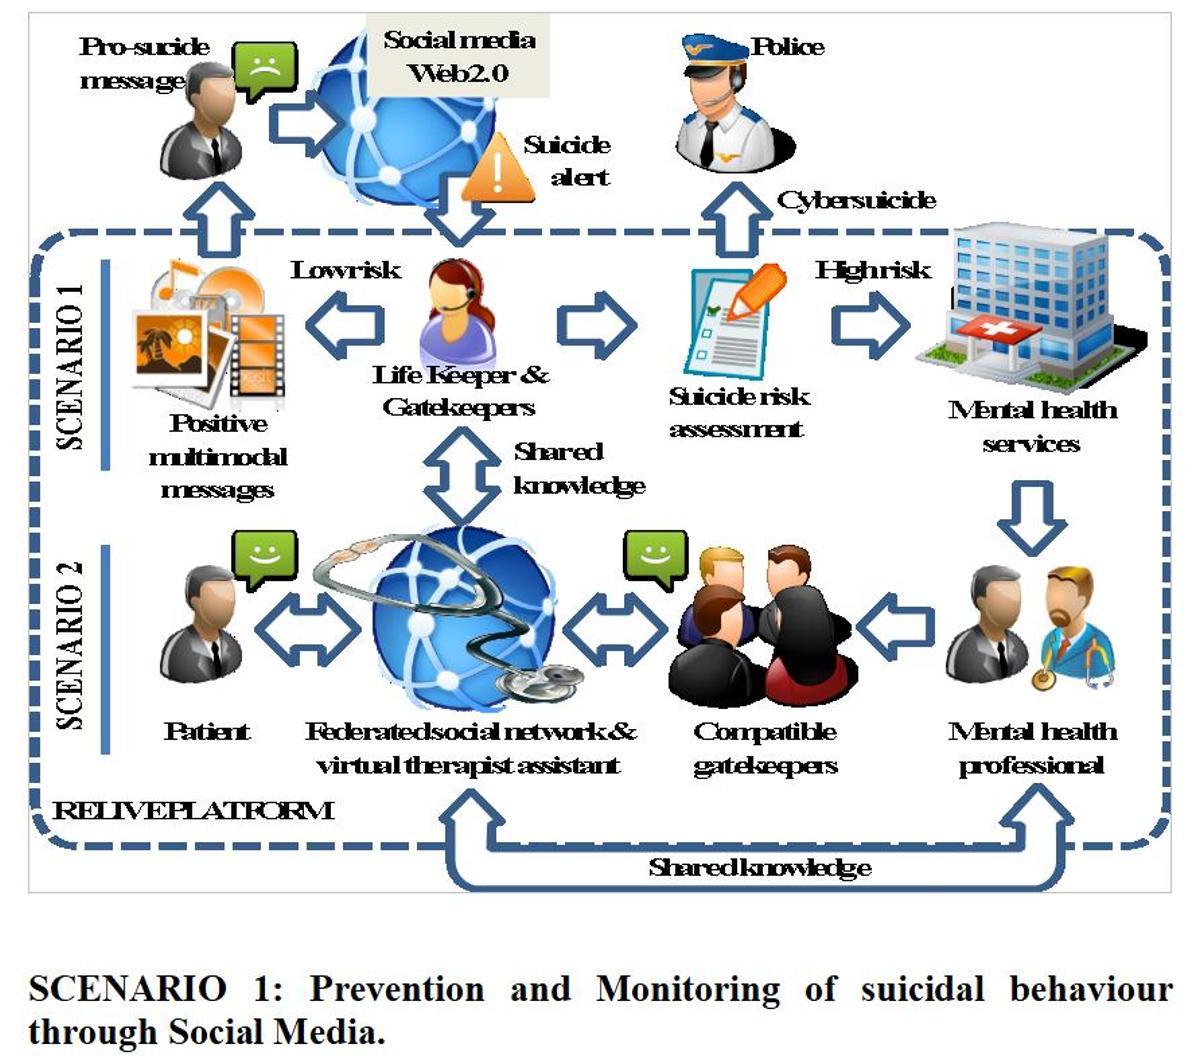

Ahora mismo la salud mental de la población preocupa enormemente. El Centro de Inteligencia Digital (CENID), impulsado por las Universidades de Alicante, Miguel Hernández de Elche y la Diputación, trabaja en el ámbito de la Psicología en un proyecto de monitorización con Inteligencia Artificial en redes sociales para la prevención del suicidio. La idea final es reconocer los mensajes de alerta que manifiestan las personas a través de sus redes, frases como "ya no puedo más", o "estoy agotado de la vida".

A través de IA se hace un rastreo en las redes para localizar esos mensajes, poder avisar a los organismos que puedan intervenir y elaborar patrones de personas en riesgo para evitarlo. El proyecto Life!, del grupo de procesamiento del lenguaje y sistemas de información (GPLSI), forma parte de los que el CENID saca a concurso y ha sido aceptado.

Una de las imágenes del proyecto de IA para prevenir el suicidio del CENID

"Haremos dos acciones. Una es escuchar lo que dice la gente para detectar posibles formas de expresar que su salud mental no está bien; y poder activar un modo de contactar con recursos como el Teléfono de la Esperanza. Otra de las vías es monitorizar a gente que ya está bajo control médico en redes sociales abiertas. La bibliografía señala que personas que se quieren suicidar escriben un documento o alguna manifestación antes, transmiten mensajes como mi vida no tiene valor o estoy hundido. Se le manda alarmas a los médicos para que puedan actuar", explica Andrés Montoyo, catedrático de la UA y director de Proyectos.

"Haremos dos acciones. Una es escuchar lo que dice la gente para detectar agresividad en el lenguaje o posibles formas de expresar que su salud mental no está bien; y otra monitorizar a gente que ya está bajo control médico en redes sociales abiertas"

En este marco, se aplican unas técnicas con Inteligencia Artificial para poder detectar los sentimientos en las frases de las personas y clarificar si es un lenguaje depresivo o agresivo que anticipa un hecho autolítico. "A partir de esa información, que la relacionamos con grafos, somos capaces de sacar alertas y poder ayudar a los profesionales a detectar que esa persona está en una frase temprana o terminal de su enfermedad mental".